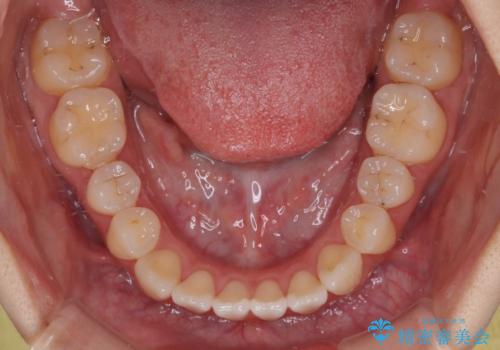

オープンバイトは舌の突出癖により誘発され、治療後も突出癖が残っている容易に後戻りしてしまいます。

治療期間を短縮するためにも、舌突出癖の改善が極めて重要となります。

特にインビザラインではIPRという歯と歯の間を削る処置を多用するため、後戻りによりスペースが生じやすくなるため、治療初期段階での舌のトレーニングが必須となります。